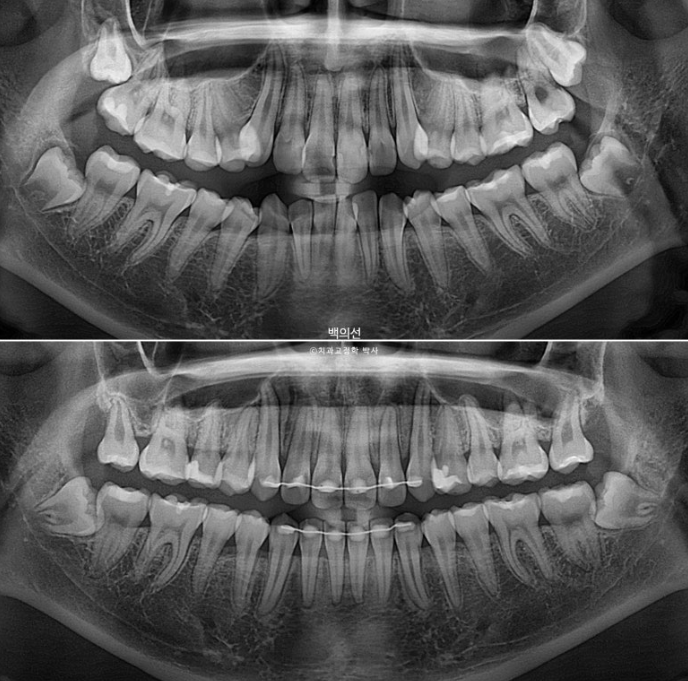

23.05~25.07

파란화살표는 사랑니입니다.

2년 2개월간 치근흡수는 없으며 치근평행도는 좋습니다.

특히 송곳니 덧니 쪽으로 쓰러져 있던 송곳니와 작은어금니 뿌리 치축 개선이 눈에 띕니다.